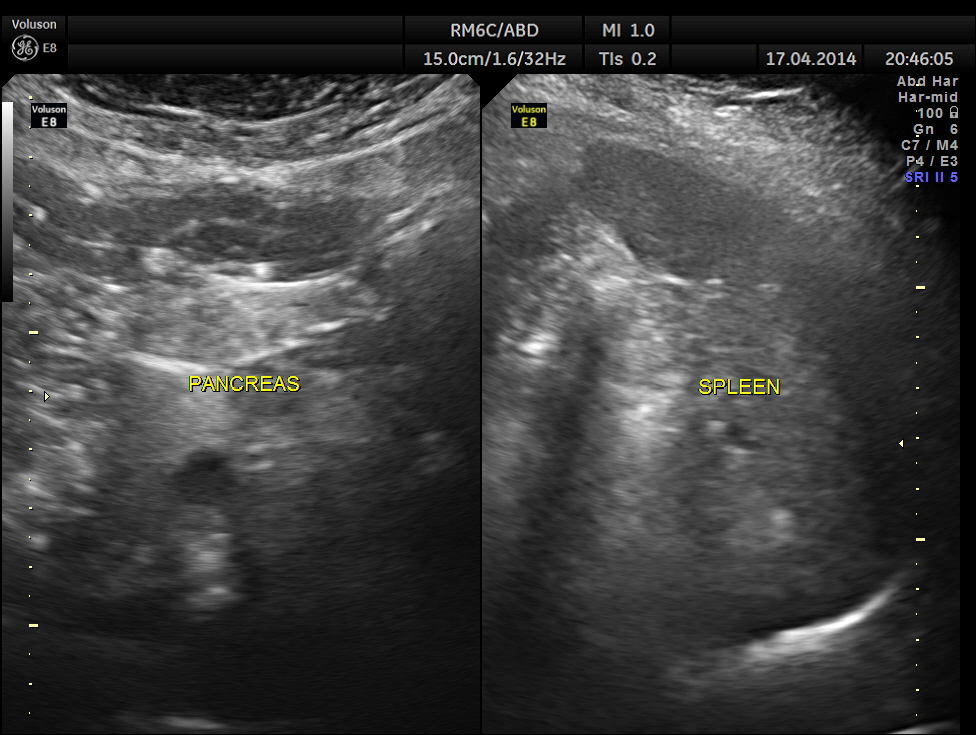

Two distinct mass lesions were seen in the right side of the abdomen in the lumbar and hypochondriac regions . Though they appeared distinct from the liver , it was a bit confusing.

The mass lesions are seen below.

Thw two masses seen out of the uterus and mainly in the right upper quadrant are shown below.

The ultrasound gave us a few inconclusive findings . Uterus was massively enlarged ; a large fibroid was seen ; adenomyosis was seen ; endometrium was thickened ; two large mass lesions were seen in the right upper quadrant and right lumbar region . But it was difficult to ascertain the origin of these extra uterine masses .